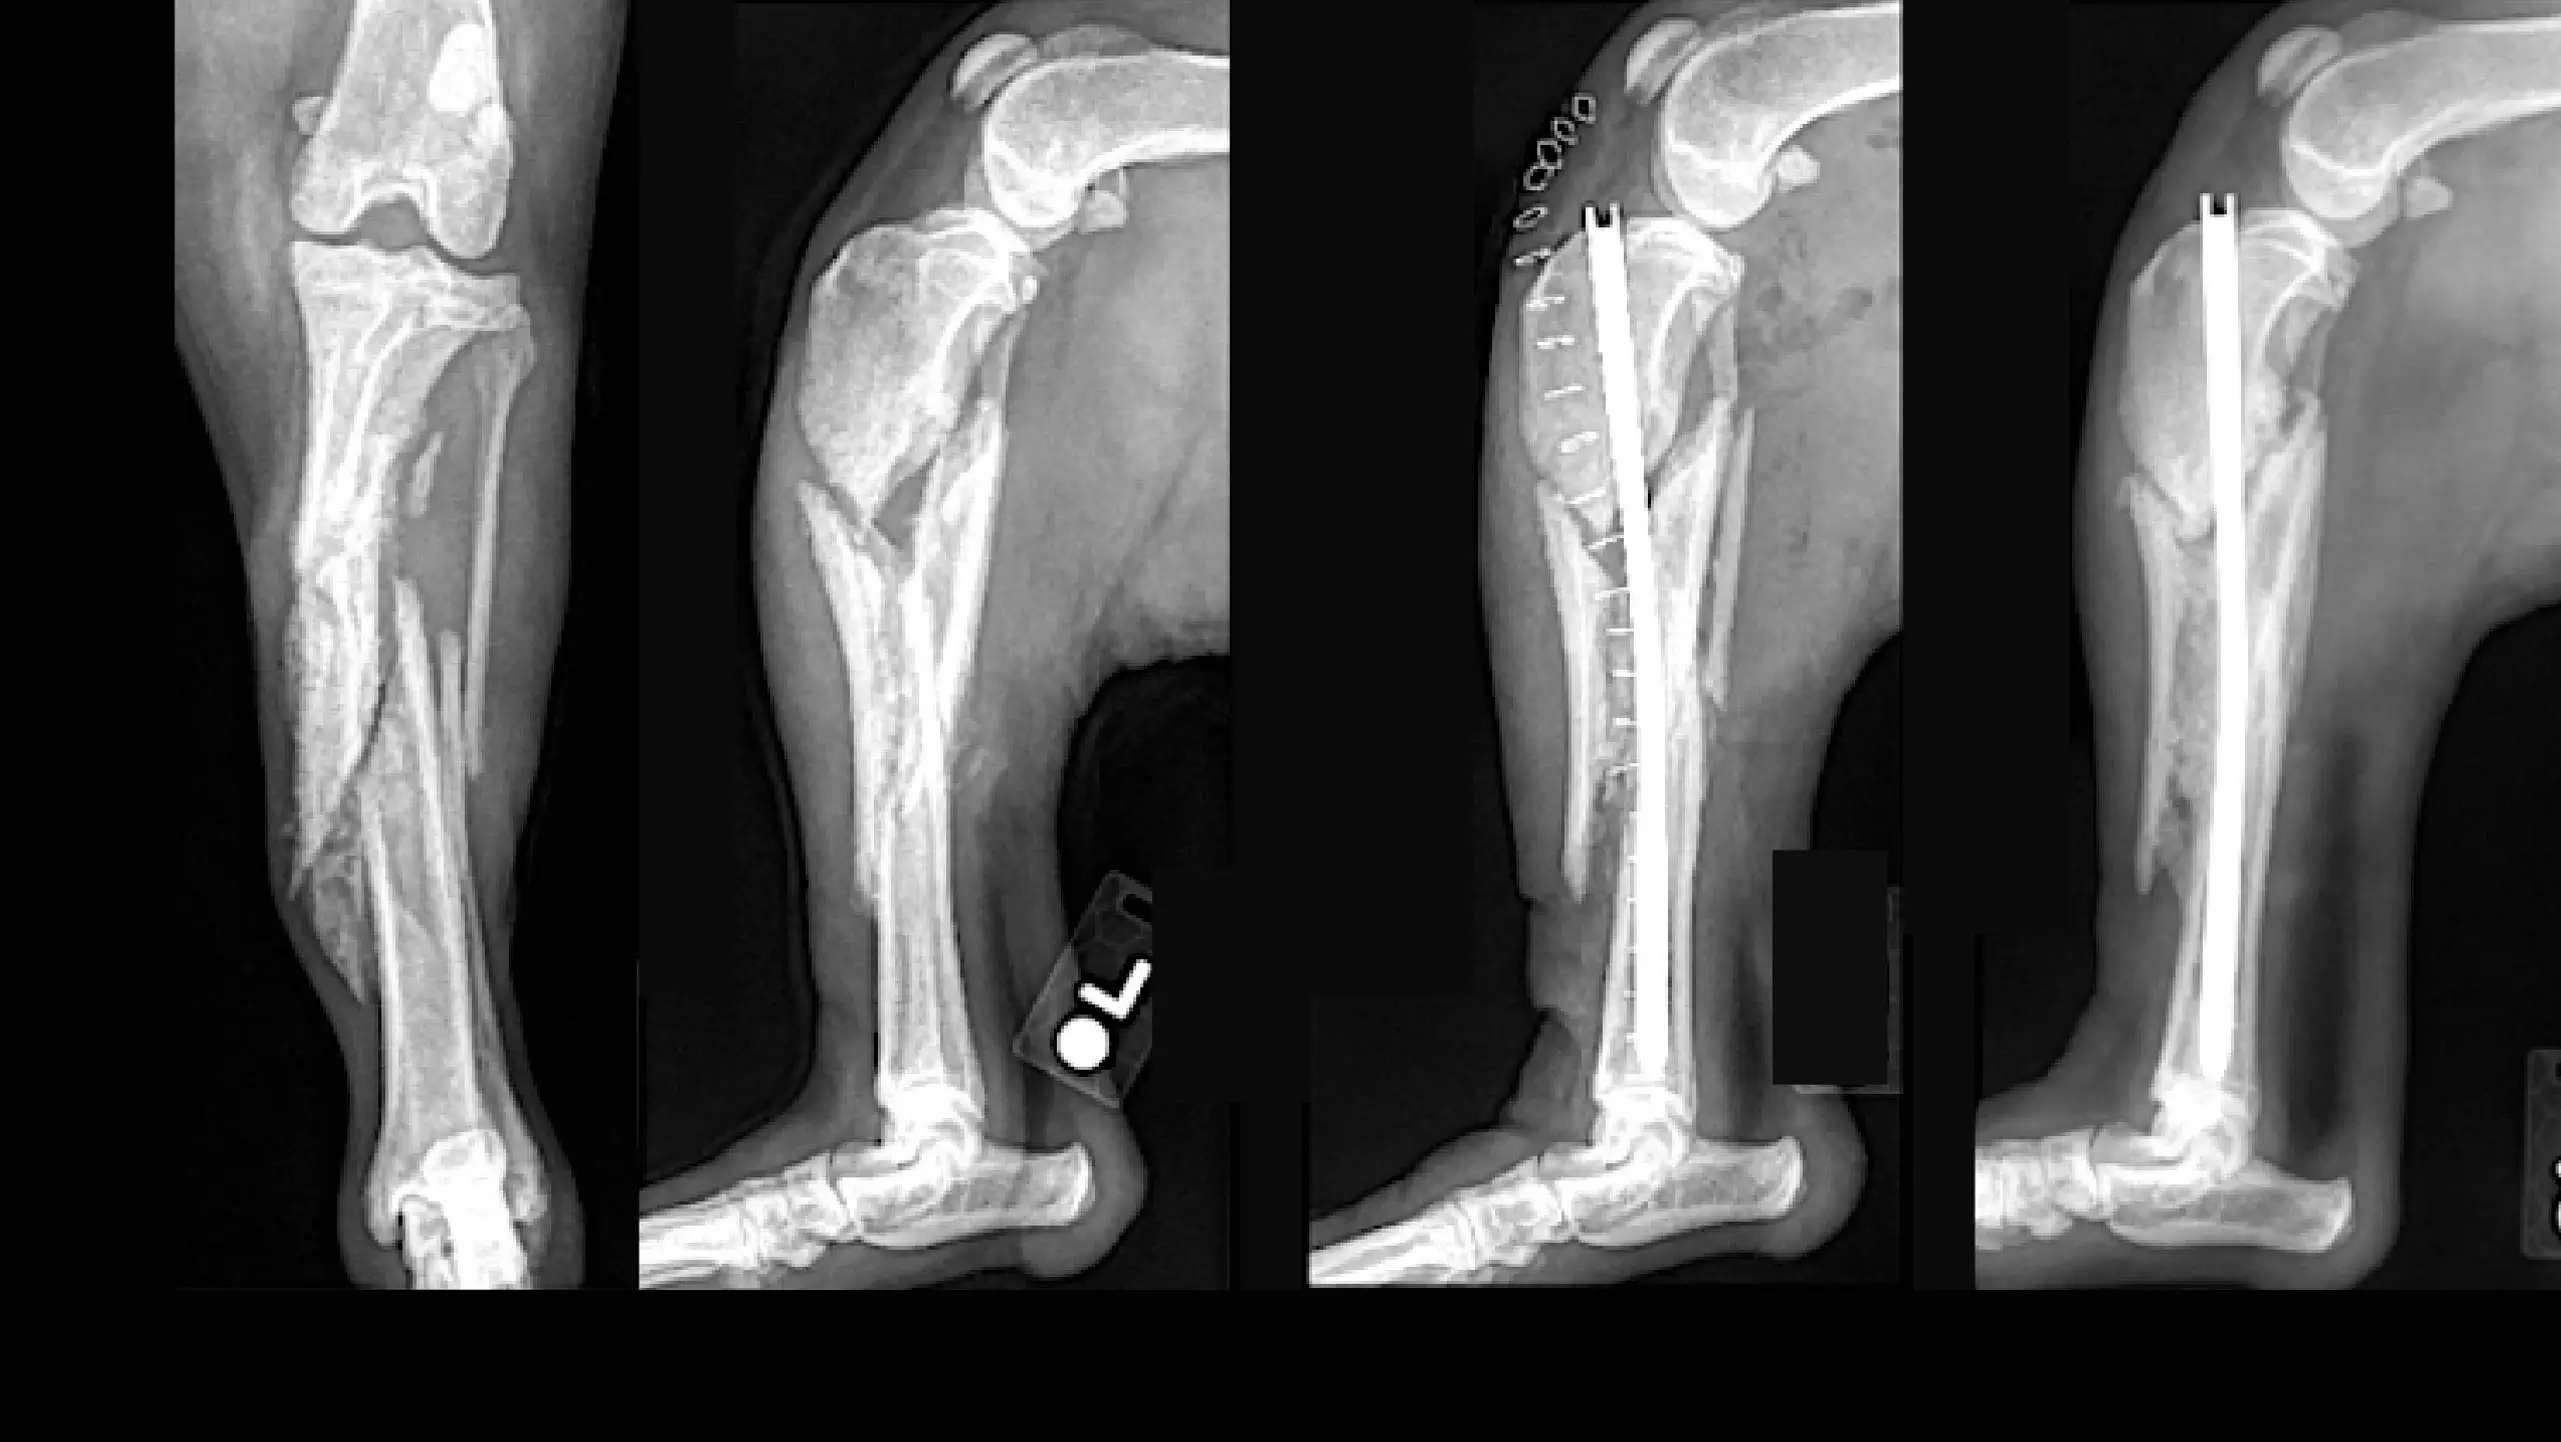

Orthopedic Trauma & Minimally Invasive Fracture Repair

CrCL Tear (TPLO)

Distal Femoral Osteotomy for Comprehensive Treatment of Medial Patella Luxation